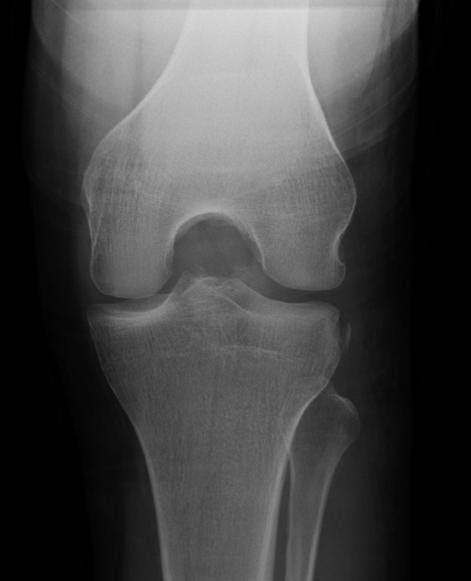

Pop Goes the Knee

Pop Goes the Knee Author: Tyler Jackson, MD, CAQ-SM Peer-reviewer: Terese Whipple, MD, CAQ-SM Final editor: Alex Tomesch, MD, CAQ-SM A 25-year-old male presents with right knee pain after a bicycle accident in which his knee twisted after planting his foot while falling off the bicycle. He also reports his knee occasionally “locks” when trying to ambulate since the injury. ROM is restricted with knee extension and flexion. Image 1 and 2. MRI R Knee (Sagittal and Axial PD) Case courtesy of Dr. Varun Babu, Radiopaedia.org, rID: 56916 References: [1][ Chambers HG, Chambers RC: The natural history of meniscus tears . J Pediatr Orthop. 2019, 39:53-5. [2] Jarraya M, Roemer FW, Englund M, et al.: Meniscus morphology: does tear type matter? A narrative review with focus on relevance for osteoarthritis research. Semin Arthritis Rheum. 2017, 46:552-61. [3] Esparragoza-Montero R, Rodriguez-Diaz J, Lanier- Dominguez J, et al. Evaluation of meniscal morphology and relation between the diagnostic findings of magnetic resonance imaging and arthroscopy in lesions of the knee. Invest Clin 2009;50(1): 35-44.

Read More...